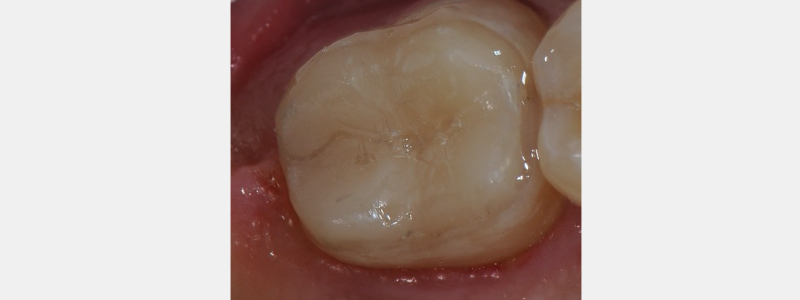

Challenges with retention form may be overcome in conservative tooth preparation by taking advantage of adhesive dentistry and the enamel/dentin complex. Provisional restorations can be retained predictably by strategically “spot etching” enamel and dentin.

As shown in Fig. 4, a definitive and contained area of enamel and dentin is etched on both the buccal and lingual aspects. Care is taken not to include the marginal areas of the tooth preparation. The circumference e of the etched surface needs to be no larger than 2-2.5 mm. This “spot” is the “retentive key” to maintaining the provisional over time.

After 30 seconds, this etchant is rinsed, and the enamel and dentin primers are placed. Self-etching materials must be avoided, as the entire enamel/dentin matrix may be bonded to the provisional.